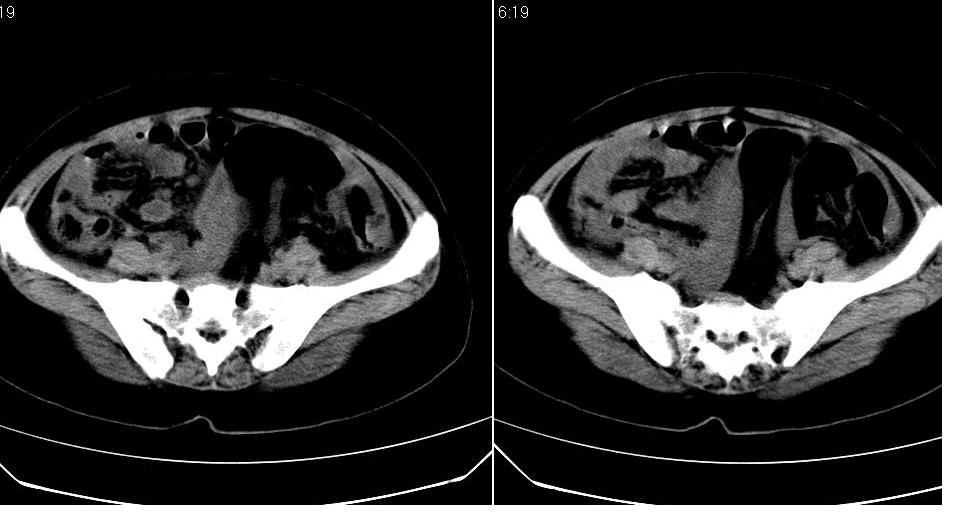

盆腔及腹腔积液,原因待查。

结核性腹膜炎可能,